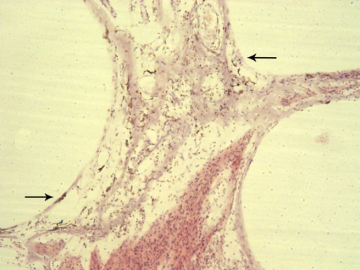

Immunohistochemical visualization of hyalinization

Fig 4. Immunohistochemical visualization of hyalinization (arrow)

Immunohistochemical study of the cause of sensorineural hearing loss due to cochlear otosclerosis. In 1969 this laboratory reported, in the face of much controversy, for the first time a relationship of sensorineural hearing loss and the amount of otosclerosis involving the cochlear capsule. The reason for the hearing loss has yet to be determined. However in severe cases of hearing loss there are changes in the spiral ligament (hyalinization signifying aseptic cellular death) seen in no other pathological conditions affecting the inner ear. We hypothesize that the same enzymes, that are responsible for the normal bone dissolution that occurs as the otospongiosis advances through the cochlear capsule, diffuse into the spiral ligament result in cell death and replacement with hyaline and a toxic suppression of the function of the organ of Corti. We are currently investigating (using immunohistochemistry (Fig 4)) various enzymes that might be responsible for the hyalinization and cochlear malfunction.